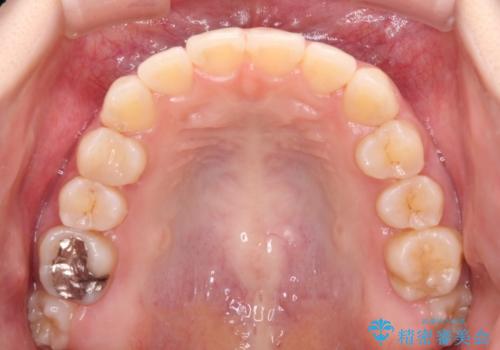

順調に後方移動することができ、わずか1年強で治療を終えることができました。

顎骨が小さいので第二大臼歯が欠損しても負担は少ないと思いますが、奥歯でもっとしっかりと咬みたいということであれば、インプラント補綴治療を4本分行うこととなります。